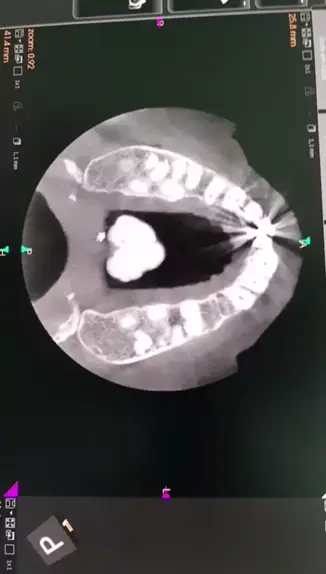

Tc.maxila Torus